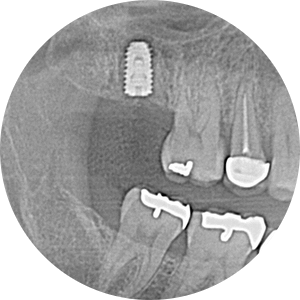

그래도 아직 임플란트 수술까지는 무서워하시니 수술은 다시 수면치료

수술도 잘 끝나셨고 자주 보니 더 친해지고 해서 더 용기내서 잇몸이 많이 부어서 잇몸치료가 필요한데 비수면으로 진행해보자고 말씀드리고 당일 도포마취, 무통마취 내가 할 수 있는 조치는 다 해서 무사히 첫 번째, 두 번째 잇몸치료를 마쳤다...

수면치료가 아니면 치과치료를 못받겠다던 환자분이 비수면으로 마취주사의 두려움을 이겨낼 때 나도 같이 큰 산을 넘은 느낌.. 이제 치과도 무서워하지 않고 자주 오실 수 있게 된 것 아닐까.. 기대해본다.